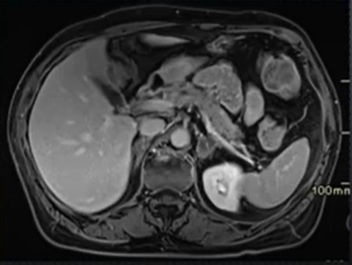

Lésions surrénaliennes